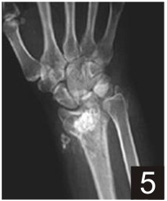

Indications for use:

Product Presentation

|

B-OstIN Granules |

B-OstIN Rod |

B-OstIN Block |